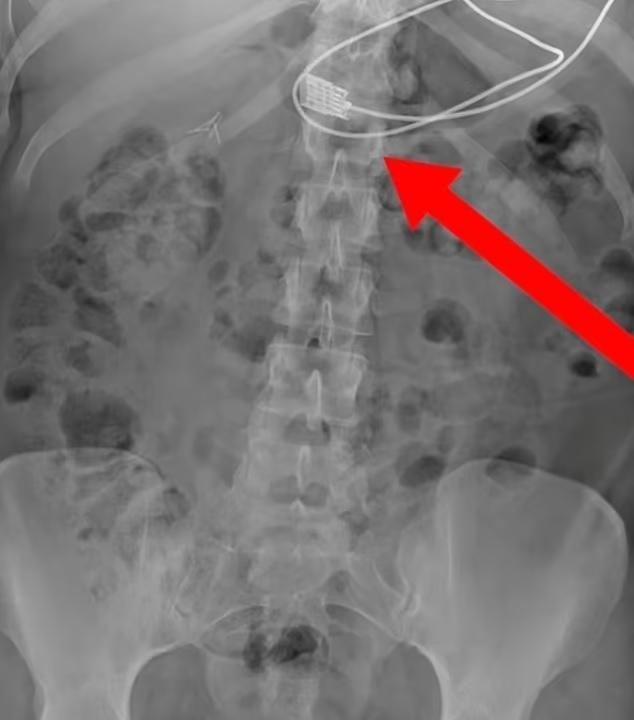

X光圖像顯示,充電接頭卡在上食道喉嚨位置。(互聯網)

英國《每日郵報》報道,波蘭西南部城市弗羅茨瓦夫(Wroclaw)的急救組織「Ready to Rescue」在Facebook公布這案例。從X光圖像可見,女子食道裡有一條長長的iPhone充電線,向下伸延至胃部。因充電接頭卡在上食道喉嚨位置,導致女子呼吸困難,她感到幾乎窒息,於是報警求助,救護員接報到場,將她送院。女子在急症室接受手術把充電線取出後,已康復出院。